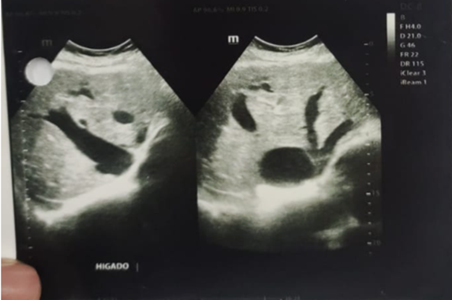

Exámenes complementarios: Electrocardiograma, evidencia fibrilación auricular, bloqueo completo de rama derecha, trastorno de la repolarización ventricular, Figura 1. Ecocardiograma reporta FEVI: 39%, rectificación del septo interventricular por sobrecarga de cámaras derechas, aumento del volumen atrial derecho, discreta estenosis mitral, válvula tricúspide de implantación baja, anomalía de Ebstein, reflujo tricúspide importante, hipertensión pulmonar moderada, formen oval patente, Figura 2. Radiografía con proyección posteroanterior de tórax reveló cardiomegalia grado IV, Figura 3. Ecografía de Abdomen, concluye dilatación de las venas hepáticas secundario a falla cardíaca congestiva, asociado a leves cambios en la eco textura del parénquima hepático por lo que se debería considerar hepatopatía congestiva, además de colelitiasis, Figura 4.

Figura 4 Ecografía de Abdomen, archivo de la paciente, se observa hepatopatía congestiva secundaria a falla cardíaca

Los criterios ecocardiográficos utilizados para identificar una anomalía de Ebstein abarcan el desplazamiento apical observado en las inserciones valvulares septal y posterior de la válvula tricúspide, junto con el desplazamiento del anillo tricúspide funcional en dirección anterior y descendente, lo que lleva a la atrialización del ventrículo derecho. Además, cabe destacar que la anomalía cardíaca predominante relacionada con esta afección en los pacientes recién nacidos es la comunicación interauricular (16). En nuestro caso, desde la perspectiva ecocardiográfica la paciente presentó sobrecarga de cámaras derechas, aumento del volumen atrial derecho, discreta estenosis mitral, válvula tricúspide de implantación baja e importante reflujo tricuspídeo lo que a su vez generó una hipertensión pulmonar moderada, no obstante, en la paciente también se practicó un eco de abdomen en el cual se reportó hepatopatía congestiva secundaria a una falla cardíaca intrínseca atribuida a la anomalía de Ebstein.